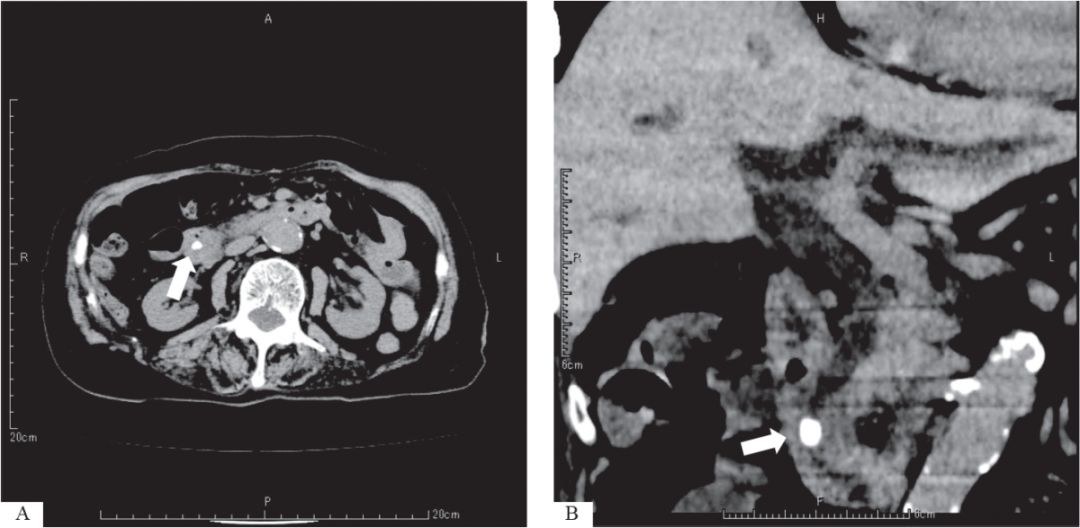

腹部CT 在检测钙化结石时相对方便且具有高灵敏度(图33-1),但其检测无钙化的小结石时灵敏度有限。

图33-1:CT图像显示十二指肠乳头处嵌顿结石A. 轴向CT;B. 多层螺旋CT。白色箭示一处嵌顿结石